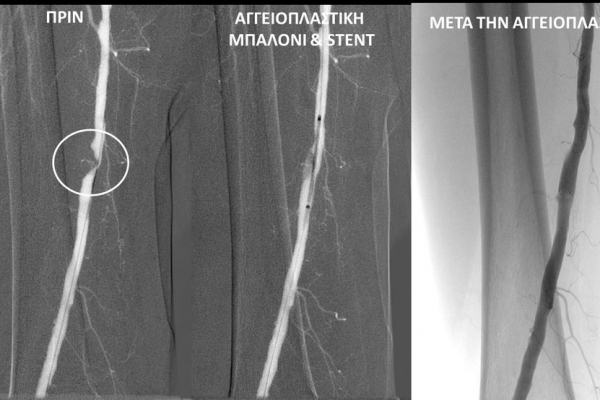

- Η αγγειοπλαστική των αρτηριών είναι μία μη χειρουργική επέμβαση που αποσκοπεί στη διάνοιξη των στενωμένων ή αποφραγμένων αρτηριών. Γίνεται με την ίδια τεχνική όπως και αγγειογραφία. Η αγγειοπλαστική των αρτηριών μπορεί να γίνει είτε με απλή διάνοιξη της αρτηρίας που εμφανίζει στένωση με μπαλόνι ή και να συνοδευθεί από τοποθέτηση ενδαγγειακής πρόθεσης (stent).